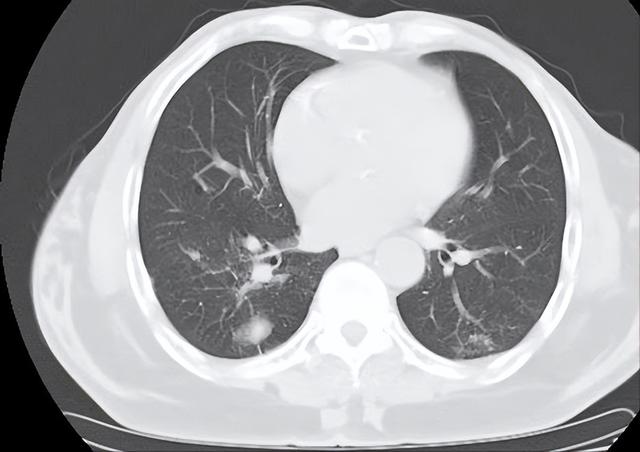

肺部结节是指肺部实质内直径小于或等于3厘米的、近似圆形的、边界相对清晰的密度增高影。当肺部出现两个或两个以上的结节时,即称为肺部多发结节。

第一,结节的大小。一般而言,结节越大,恶性可能性越高。直径小于5mm的结节,恶性可能性不足1%;直径6-10mm的结节,恶性可能性约为0.5%-2%。

直径11-20mm的结节,恶性可能性约为6%-28%;直径21-30mm的结节,恶性可能性则高达33%-64%。

第二,结节的形态。边缘光滑、圆形或椭圆形的结节多为良性;而边缘毛刺、分叶、不规则形态的结节则需要警惕恶性可能。

第三,结节的密度。纯磨玻璃密度(GGO)、混合密度的结节恶性可能性较高,而钙化、脂肪密度的结节多为良性。